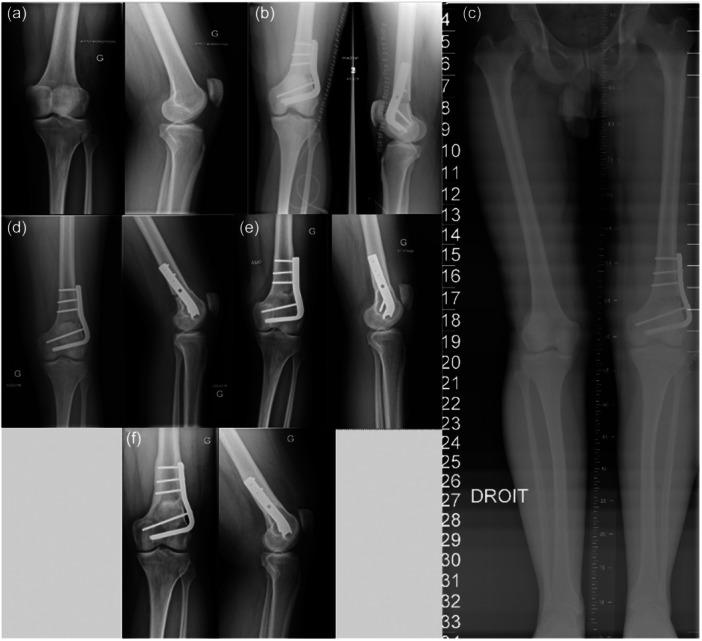

Between 1991 and 2011, 62 LOW-DFOs were performed in the same department. Inclusion criteria were all isolated LOW-DFO performed for isolated lateral tibiofemoral osteoarthritis and valgus malalignment, with a minimum 10-year follow-up. Thirty-eight patients were included, with a mean age of 48 ± 9 years. All patients had clinical and radiological assessments. The survival curves were calculated based on the following endpoints: unicompartmental or total knee arthroplasty.

The mean follow-up was 15.2 ± 4.4 [10-29] years. The mean preoperative mechanical FemoroTibial Axis (mFTA) was 188.8° ± 3.2° [184°-197°], primarily due to femur deformity (mean lateral distal femoral axis [LDFA] 83.2° ± 2.8°). Bone union was achieved in 89.5% of patients (n = 34) at a mean delay of 6.5 ± 6.7 months. The complication rate was 26% (five stiffness, one nonunion, three secondary displacements and one deep vein thrombosis). Nine revision surgeries (24%) were recorded. Survival rates at 5 and 10 years were 92.1% and 78.9%, respectively. The mean delay between DFO and total knee arthroplasty (TKA) was 11.6 ± 5.7 [1-27] years. Nineteen patients (50%) were free of TKA at the last follow-up. KSS scores were improved significantly. Return to sports was obtained in 92% of cases (n = 35), with a mean delay of 11 ± 8 months. Seventy-four per cent of patients were satisfied or very satisfied with the surgery. Eighty-four per cent would be willing to undergo the surgery again. Older age (p = 0.032) was a significant risk factor for TKA conversion.